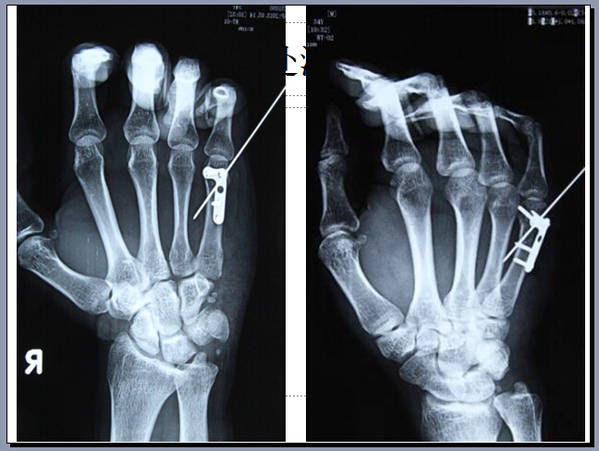

手外科会议带去一个讨论题目